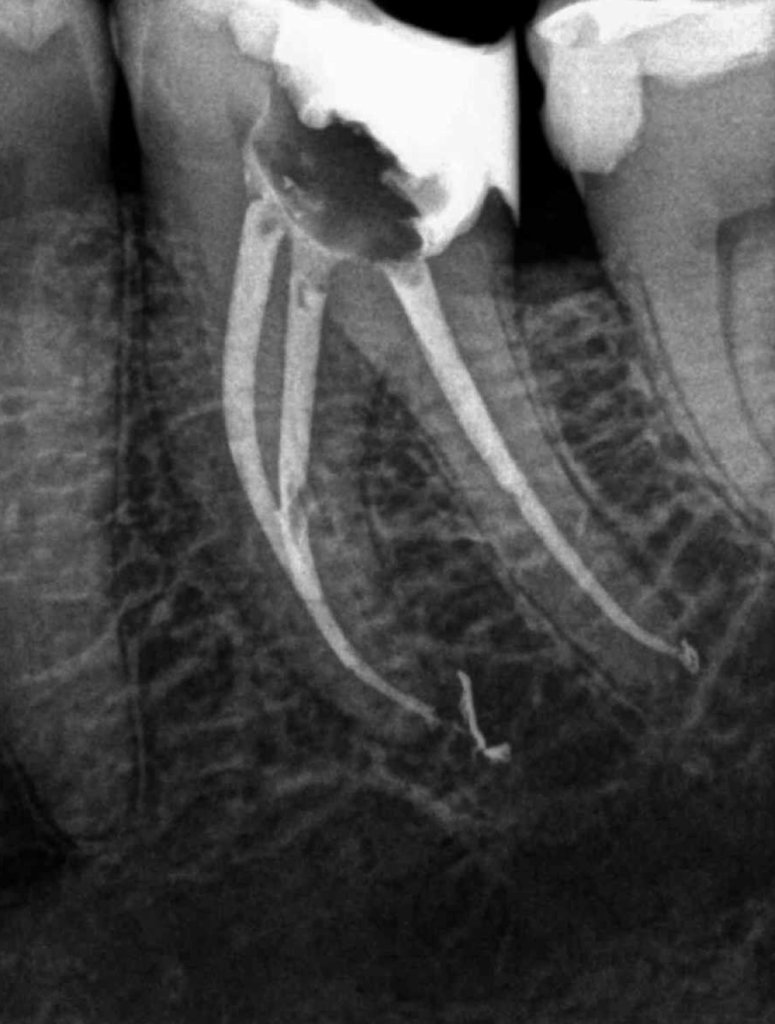

Molar inferior, conducto CM